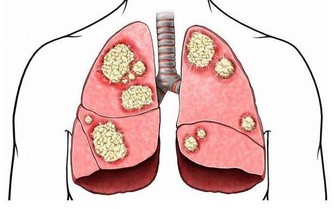

當我們談到有關女性的癌症類型時,你必然會提起乳腺癌,因為這是女性發病率最高的癌症。然而與此同時,大家一定不要忘了卵巢癌,這也是一名同樣危險的殺手,發病率也相當高。

而且,卵巢上皮癌死亡率,佔各類婦科腫瘤的首位。其死亡率如此之高,重要原因是很難早期發現。我們身邊會有一些女性知道對乳房進行自檢,卻不知道關注卵巢癌的跡象。